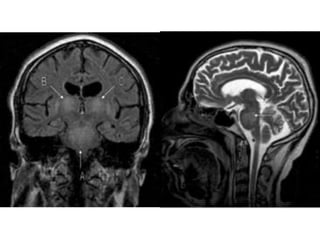

Osmotic Demyelination Syndrome

• Central pontine + extrapontine

• Over-enthusiastic correction of Na+

• In chronic hyponatraemia

– Brain tissue losses inorganic and organic solutes

– Takes few days

• Demyelination

• Pontine symptoms

– Dysarthria, dysphagia, pseudobulbar palsy

– Flaccid quaraparesis

• Extra-pontine

– Tremor, ataxia, mutism

– Parkinsonism, dystonia

• Reversible ?

– 5% dextrose and desmopressin